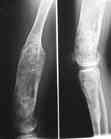

Высылаю вам фото подобной больной, у нее тоже первая попытка до меня была безуспешной.

Нужен аппарат Илизарова стабильный с множеством спиц с напайкой, временной фиксацией колена аппаратом на голени. Наверное, проще первый раз начать с бедра, остеотомию выполнить прямо на уровне перехода очага в дистальный метафиз бедра. Дистракционный остеогенез вызовет перестройку хрящевой ткани в костную. Понадобится еще пара этапов.